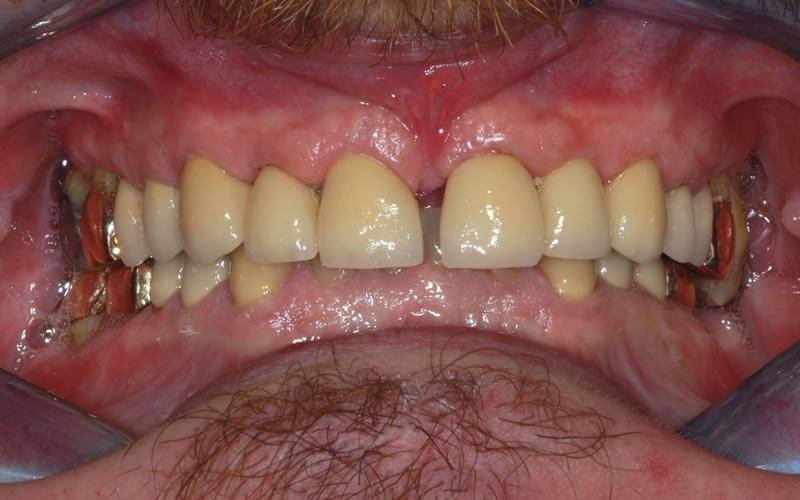

Case Studies

Dental Crowns (7 images)

Upper crowns and lower composites (4 images)